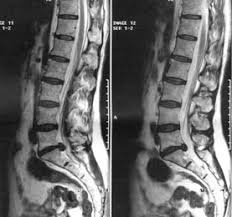

These levels were investigated in this study as degeneration occurs most often and earliest in these three lower vertebral levels 17 fourth and fifth lumbar spine vertebrae and the first sacral vertebra were evaluated for disc bulging and protrusion See Lumbar Artificial Disc Replacement for Chronic Back Pain A high intensity zone HIZ is seen at L4-L5 Depending on the extensiveness. Es wurde eine ausgeprägte Osteochondrose mit Pseudolisthese und Bandscheibenprotrusion L45 diagnostiziert. Bei einer Bandscheibenprotrusion können die Nervenwurzeln hier blau geschädigt werden.

Die Schmerzsymptomatik wird durch die Vorwölbung ausgelöst die gegen einzelne Nerven Nervenbündel Nervenwurzeln oder auf das Rückenmark drücken kann. Die Schmerzsymptomatik wird durch die Vorwölbung ausgelöst die gegen einzelne Nerven Nervenbündel Nervenwurzeln oder auf das Rückenmark drücken kann. Eine Bandscheibenvorwölbung nennt man in der medizinischen Fachsprache Bandscheibenprotrusion - dabei wölbt sich der Faserring der Bandscheibe in Richtung des Nervenkanals vor. Bei dieser Erkrankung der Wirbelsäule rutscht der innere gallertartige Kern Nucleus pulposus aus seiner ursprünglichen Position. Sie kann so zum Beispiel zu den typischen Rückenschmerzen bei einem Hexenschuss führen. Wenn der Gallertkern fast bis zum äußersten Bereich des Faserrings vordringt der bis zum Außenumfang des Wirbelkörpers vorsteht ohne das hintere Band zu dehnen. Die Bandscheibenprotrusion ruft daher wenn überhaupt meist nur Wirbelsäulensymptome hervor. Computertomographisch zeigten sich ein Vakuumphänomen und eine Bandscheibenprotrusion mit Forameneinengung rechts L45 bei. Welches mögliche Symptome sind erfahren Sie in diesem Ratgeber.

Wenn der Gallertkern fast bis zum äußersten Bereich des Faserrings vordringt der bis zum Außenumfang des Wirbelkörpers vorsteht ohne das hintere Band zu dehnen. Die Bandscheibenprotrusion der LWS beschreibt nun den Zustand in dem sich einer der Kerne einer Bandscheibe nach hinten vorgewölbt hat und auf Teile des Rückenmarks oder zentrale Nerven drückt. Diese unterscheidet sich vom Bandscheibenprolaps im. Der dritte Grad erzeugt Lombalgie Kreuzschmerzen und Ischialgie. Die Bandscheibenprotrusion auch Bandscheibenvorwölbung oder inkompletter Bandscheibenprolaps ist eine mit dem Alter zunehmend häufiger zu beobachtende Veränderung im Bereich der Wirbelsäule. Die Symptome ähneln dann denen eines Bandscheibenvorfalls. Je nach Lage der Vorwölbung und der betroffenen Bandscheibe haben Menschen mit Bandscheibenprotrusion überhaupt keine Beschwerden die Schmerzen treten örtlich begrenzt.